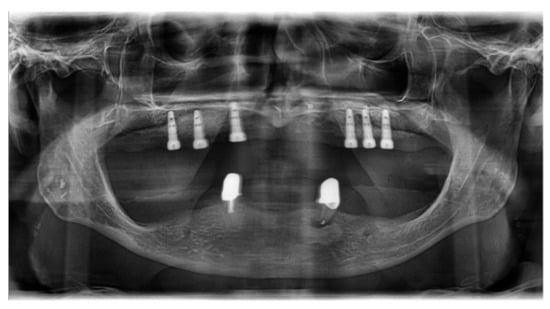

2.2. Clinical Case Vignettes

2.4. Description of the Clinical Case Vignettes